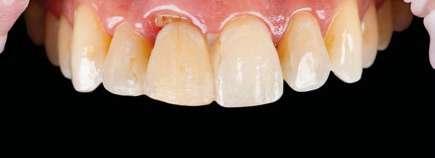

na paciente de 35 años (Figura 1) fue remitida a la Clínica de Odontología Reconstructiva de la Universidad de Zúrich debido a una infección crónica en el diente 11 y con expectativas estéticas muy altas. El diente 11 había sufrido un trauma hace 10 años y había sido tratado con multiple endodoncias sin éxito. El diente presentaba un absceso bucal (Figura 2), una bolsa periodontal aislado de 9 mm, y una ausencia de la tabla vestibular ósea (Figura 3). El diagnóstico se estableció como una fractura radicular vertical, lo que resultó en un pronóstico pobre. El plan de tratamiento consistió en una extracción combinada con preservación alveolar, colocación de implante diferido con injerto de tejido conectivo, una corona cerámica implantosoportada en 11 y una nueva carilla de cerámica para el diente 21.

El diente 11 fue extraído (Figura 4), seguido por la preservación alveolar. Se realizó un injerto pediculado de espesor parcial rotado del paladar (Figura 5), junto con una membrana de colágeno reabsorbible, un xeno-injerto bovino y cianoacrilato sellando al alveolo (Figura 6). La provisionalización consistió en un puente adhesivo de resina con dos alas de metal. El alveolo se dejó cicatrizar durante 6 meses, después de los cuales se tomó una impresión digital así como un escáner CBCT (Figura 7). Se llevó

a cabo una planificación digital para una cirugía guiada de implante en una posición protéticamente ideal (Figura 8). El implante 11 se colocó completamente guiado a través de una férula (Figura 9). Las dimensiones del reborde alveolar eran ideales para la colocación del implante en una posición atornillada (Figura 10), al igual que la calidad del hueso cicatrizado. Un injerto de tejido conectivo subepitelial fue estabilizado ocluso-bucalmente al implante (Figura 11) y el puente adhesivo fue recementado (Figura 12). Después de 3 meses de cicatrización, se realizó una restauración provisional y se acondicionó adecuadamente para dar forma al perfil de emergencia, imitando el del diente adyacente (Figura 13). Después de una fase provisional, se tomó una impresión analógica individualizada para el implante 11 y el diente 21 (Figura 14). El laboratorio fabricó una corona implantosoportada de zirconio con cerámica estratificada para el 11 y una carilla laminada feldespática para el diente 21 (Figura 15). Ambas restauraciones fueron colocadas en la paciente y mantenidas. La paciente quedó muy satisfecha con el resultado estético de las restauraciones (Figuras 16, 17). Después de 2 años, el implante permanece saludable con el hueso marginal estable (Figura 18) y una buena calidad y cantidad de tejido blando.

Una correcta planificación digital fue clave para definir los objetivos del tratamiento y el manejo detallado de un caso complejo en una paciente con alta demanda estética. Realizar la preservación alveolar para mejorar las dimensiones volumétricas antes de la colocación del implante facilitó una implantación

guiada sin necesidad adicional de aumento de cresta. La planificación digital con cirugía guiada permitió la implantación en una posición atornillada ideal. La fase de provisionalización consiguió dotar al perfil de emergencia de una apariencia estética y natural. Las dos restauraciones cerámicas resultaron simétricas y muy estéticas para una paciente satisfecha. 